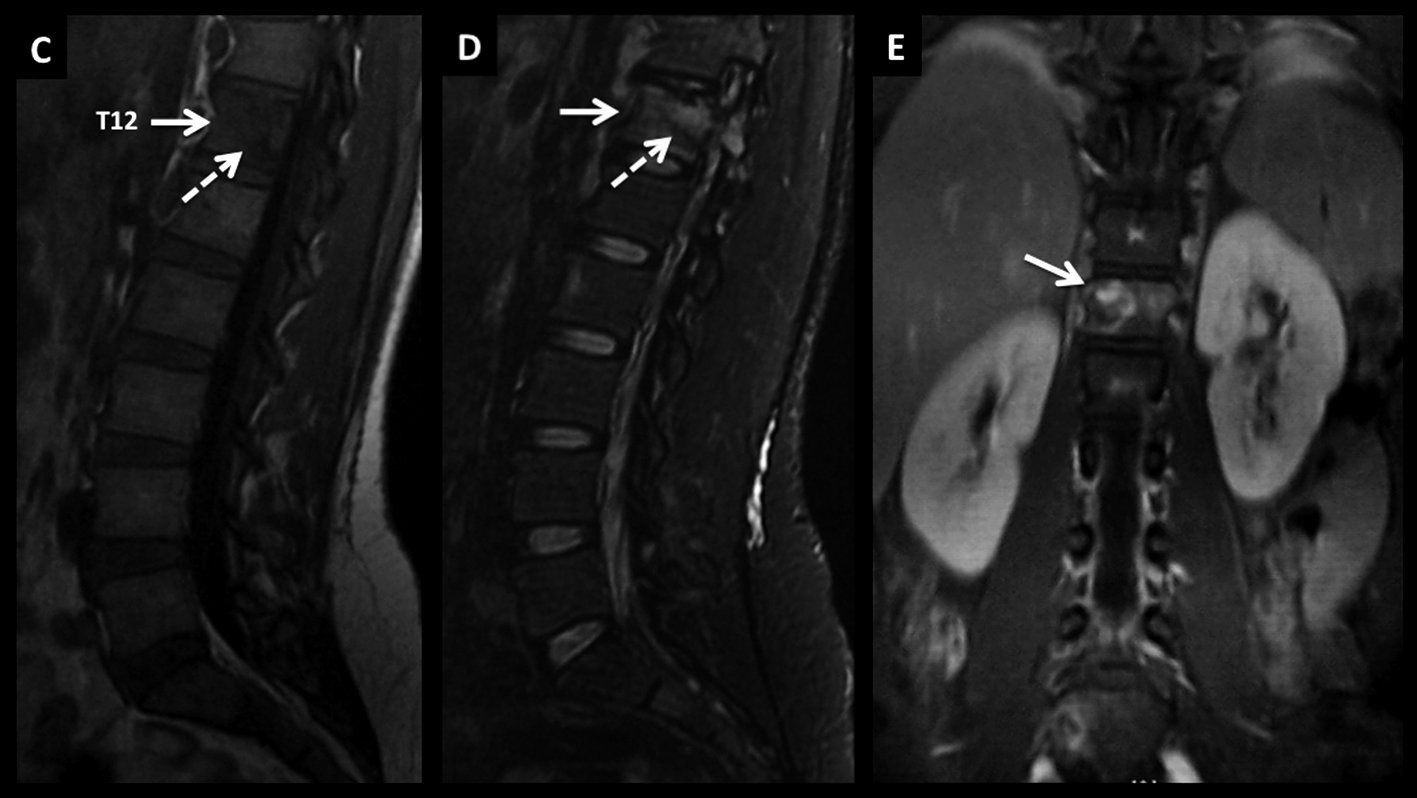

Figura 4

LNH, lesiones óseas y masa extradural, compromiso secundario.

Paciente con LNH sistémico, que presenta dolores óseos progresivos y un síndrome de medular asociado.

En RM, secuencia T2 sagital (A) se observan múltiples pequeñas lesiones óseas (*) heterogéneas, y una masa de partes blandas a nivel dorsal bajo, intra-raquídea, extradural, de baja señal en T2 con desplazamiento y compresión del cordón medular (flecha discontínua).

En secuencia T1 (B) es de baja señal y luego de administrar contraste presenta intenso realce, homogéneo (C).

LNH, lesiones óseas y masa extradural, compromiso secundario. (cont)

En el plano axial (D secuencia T2, E secuencia T1 y F secuencia T1 con contraste) se observa la masa descrita con un patrón de crecimiento que lo “amolda” al canal y se extiende a los espacios vecinos a través de los neuro-forámenes del nivel seleccionado.